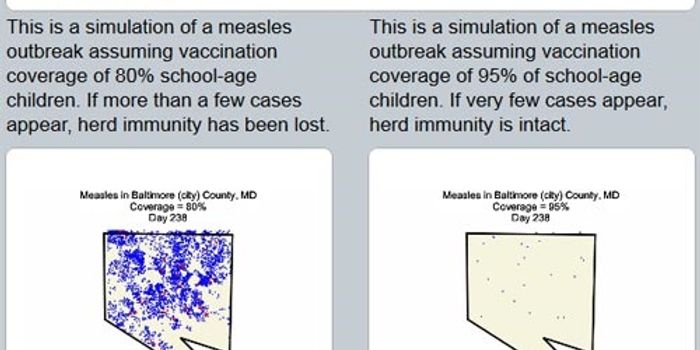

MAR 04, 2021ImmunologyUnlike social distancing, mask-wearing, and hand hygiene, vaccines are our best bet as a long-term solution to protectin ...

AUG 29, 2017InfographicsOver the years, vaccines have prevented countless cases of disease and saved millions of lives. Currently, there are ove ...